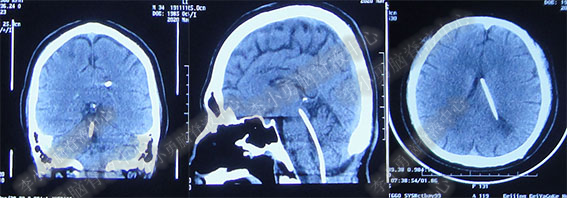

图-3:2016年9月26日头部MRI